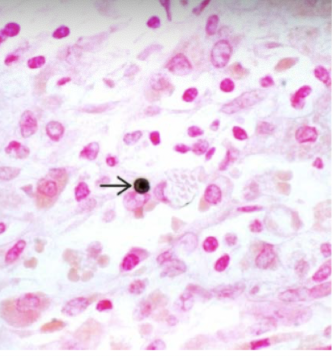

malakoplakia

distinctive chronic inflammatory reaction that appears to stem from acquired defects in phagocyte function

chronic E coli or proteus infection

renal transplant recipients! (immuno comp)

malakoplakia

sheets of large foamy macrophages with granular cytoplasm = von hansemann cells

malakoplakia

michaelis-gutmann bodies = laminated mineralized concretions resulting from deposition of calcium in enlarged lysosomes